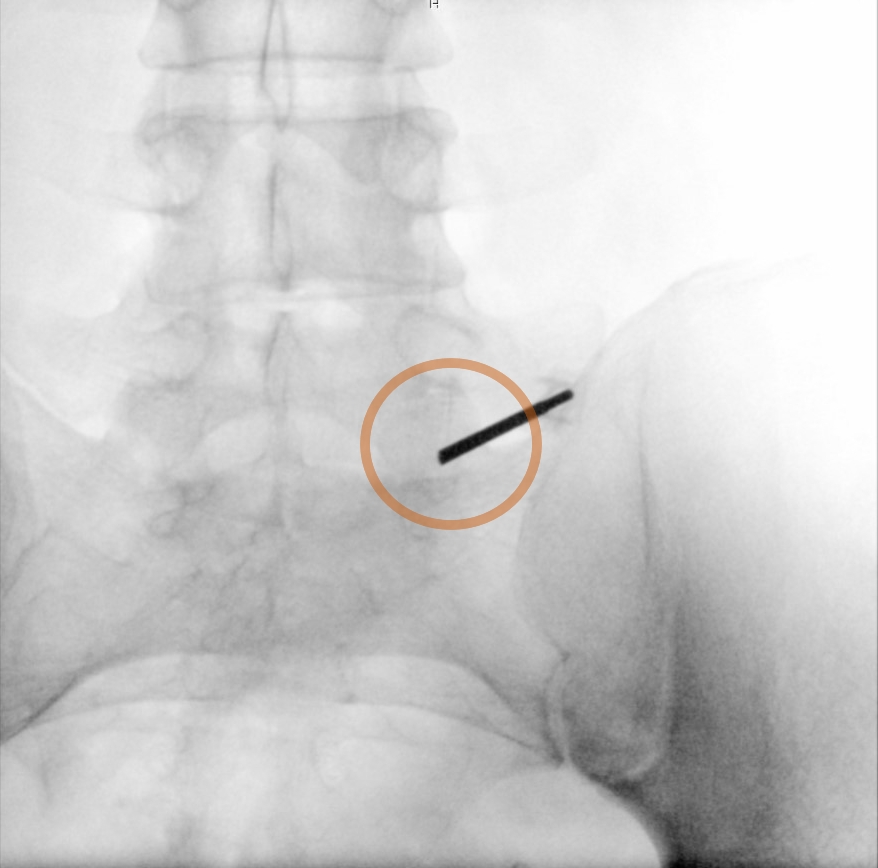

Fluoroscopic image of an inserted cold probe for cryorhizotomy at the facet joint gap (orange circle) LWK5/SWK1.